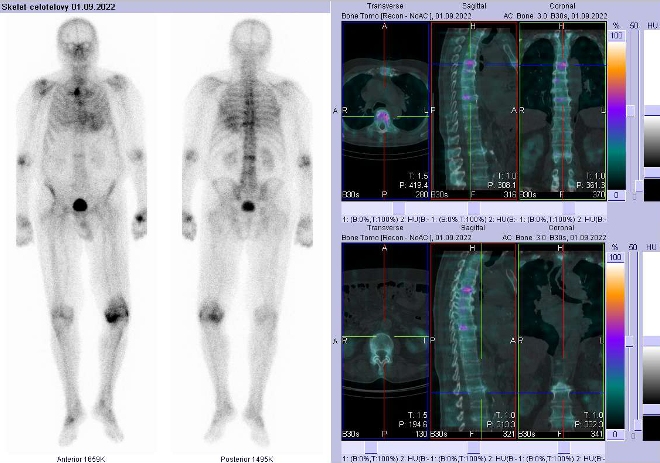

Celotělové scintigramy jsme provedli po podání 700 MBq 99mTc-oxidronátu (přípravek

TechneScan HDP firmy Mallinckrodt Medical) na hybridní tomografické scintilační kameře Symbia T2 firmy Siemens. Vyšetření jsme doplnili o dva cílené tomografické scintigramy (SPECT) krční, hrudní a bederní páteře kombinované s CT

(obr. 1-3).

/ Obr. č. 1: Celotělová scintigrafie v přední a zadní projekci a fúze obrazů SPECT a CT. Vpravo zaměřeno na ložisko v Th a L páteři.

Pozorujeme vyšší akumulaci radiofarmaka v hrudní a bederní páteři, pravém sternoklavikulárním skloubení, levém kolenním kloubu, pravém nártu, pravém ramenním a loketním kloubu, také však v myokardu.

Závěr: zvýšená osteoblastická aktivita v hrudní a bederní páteři, pravém sternoklavikulárním skloubení, levém kolenním kloubu, pravém nártu, pravém ramenním a loketním kloubu, také však v myokardu. Nález svědčí pro degenerativní, případně zánětlivé změny. Dále se pravděpodobně také jedná o transthyretinovou srdeční amyloidózu – vhodné došetření u nás s radiofarmakem

99mTc-DPD – po telefonickém objednání.